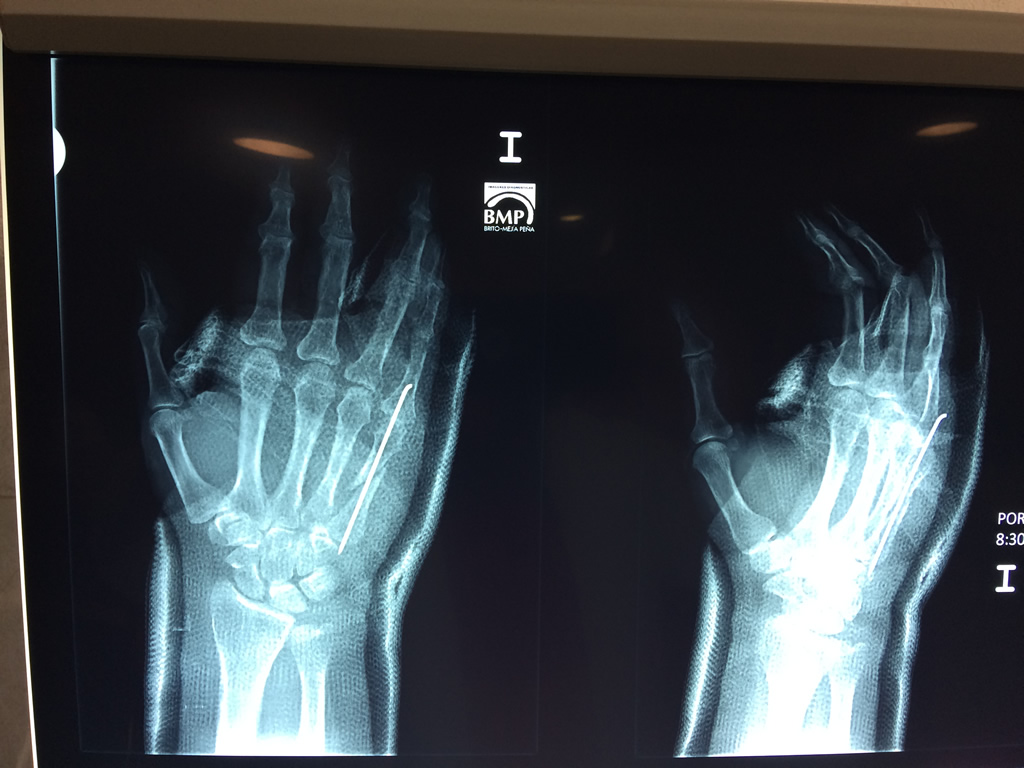

Cirugías de Codos - Cirugías de Muñecas y Manos

Los procedimientos más comunes en cirugía de la mano son aquellos destinados a reparar traumatismos, incluyendo lesiones de tendones, nervios, vasos sanguíneos, y articulaciones; huesos fracturados; y quemaduras, cortes, y otros daños de la piel.